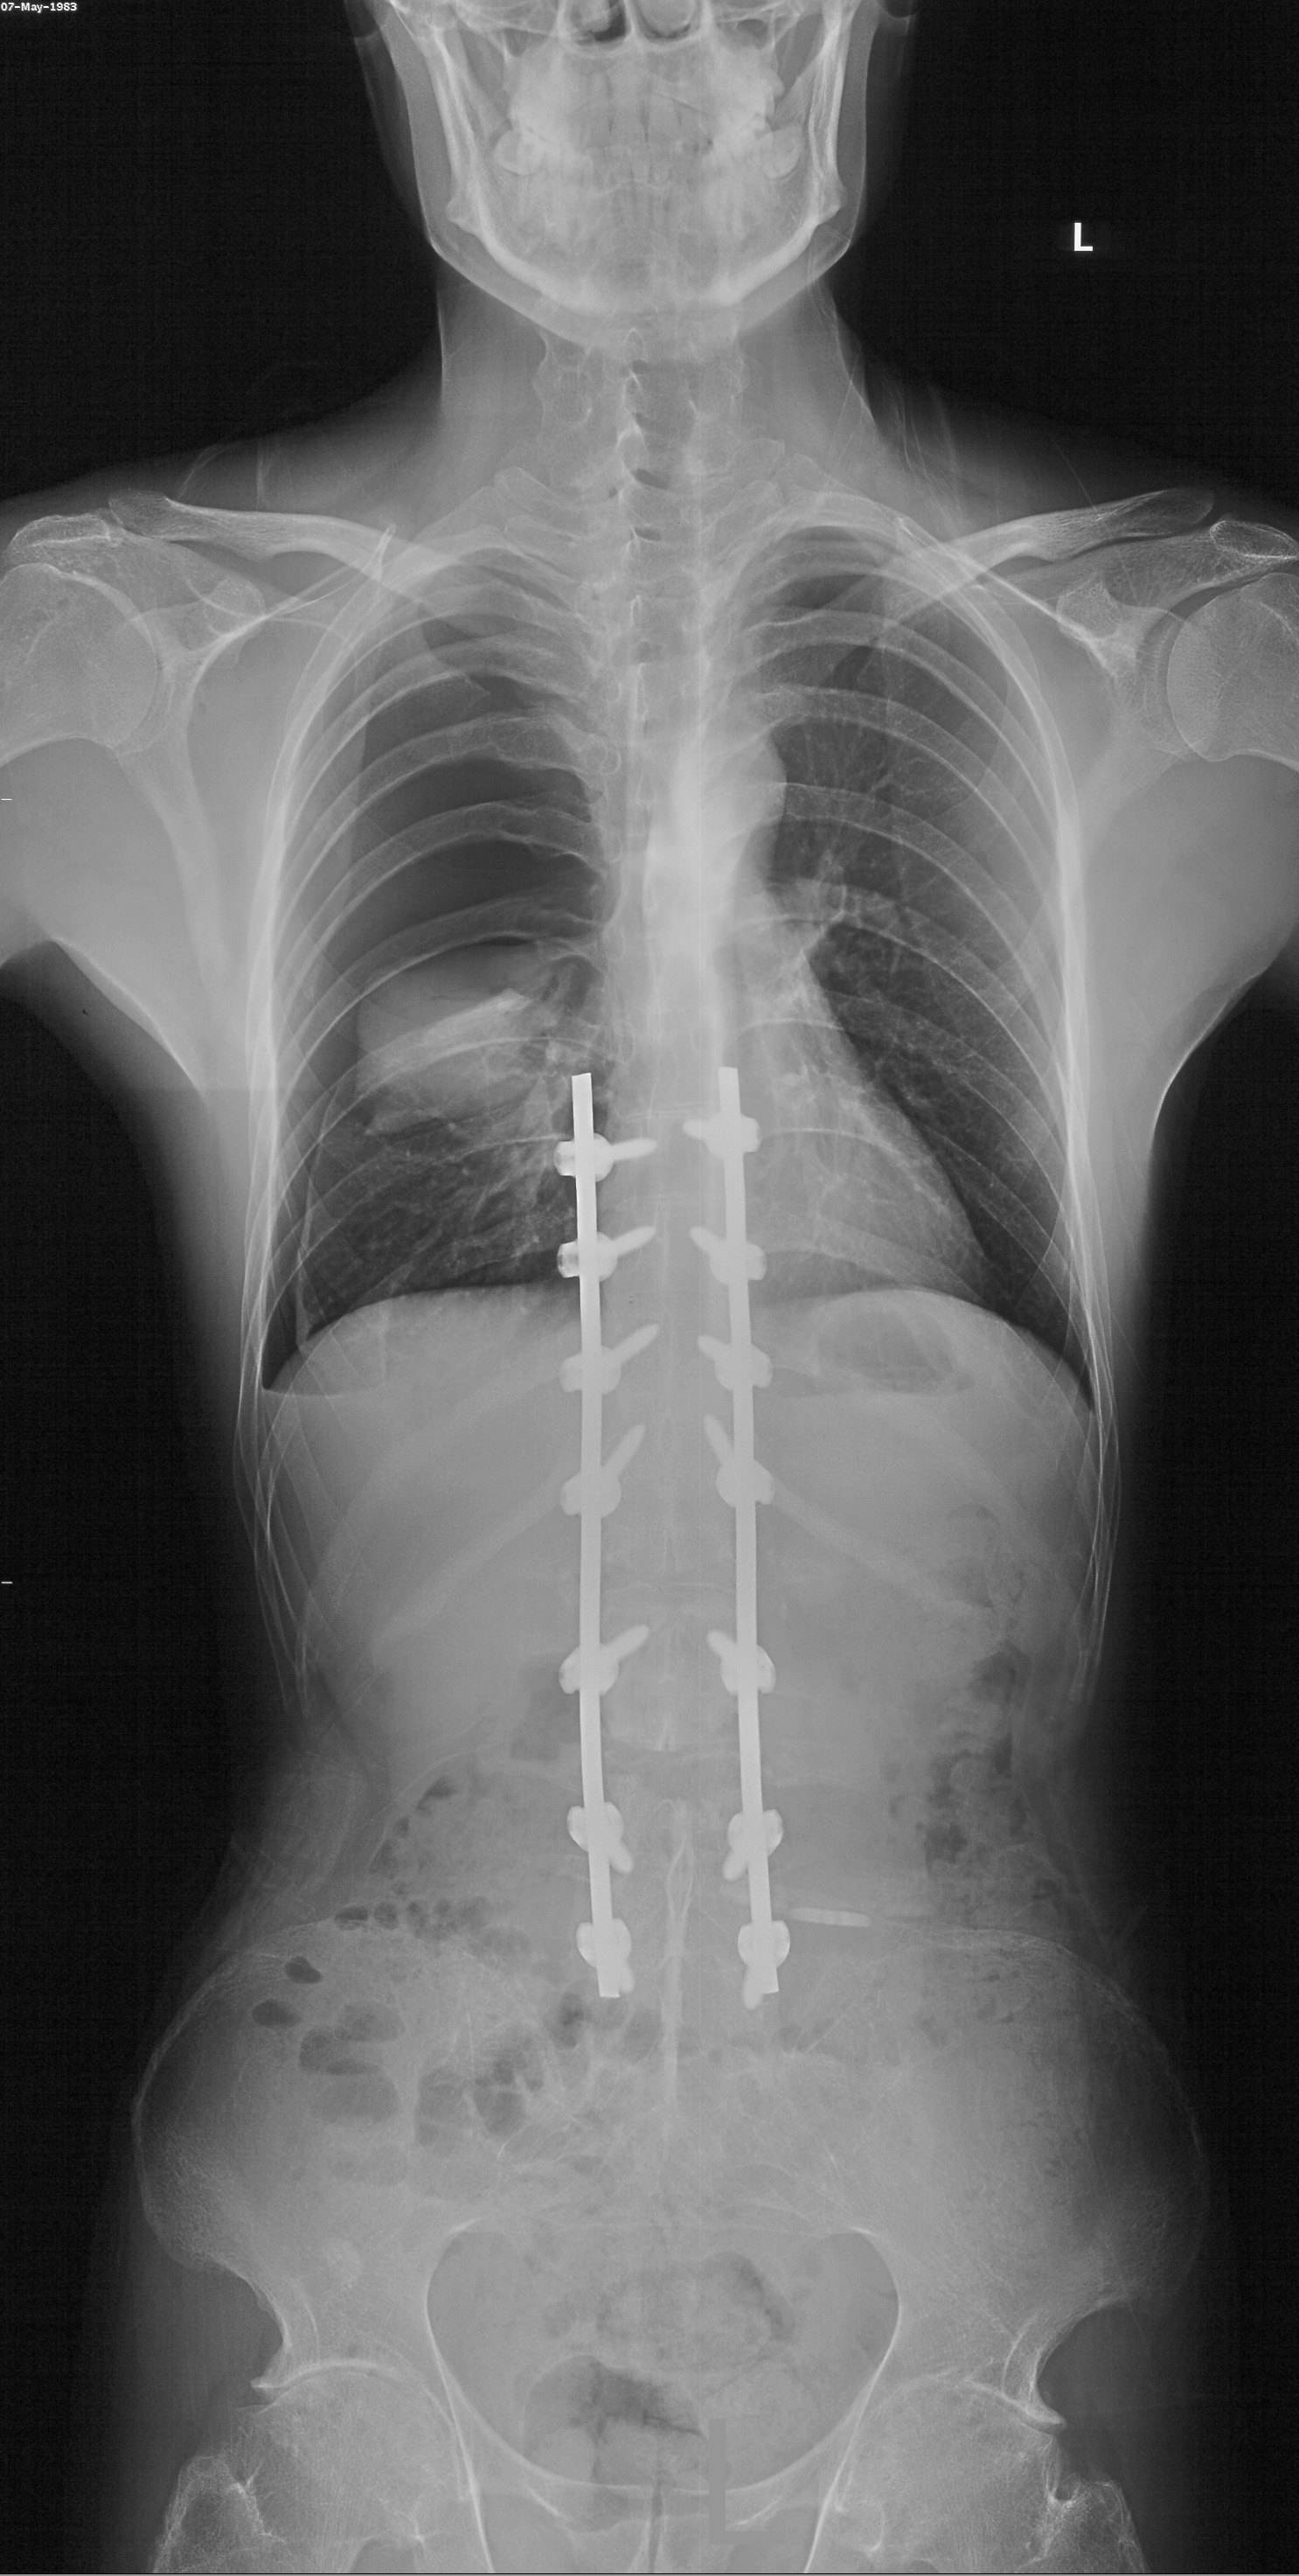

是不是手术没做好

图片尺寸2112x2816